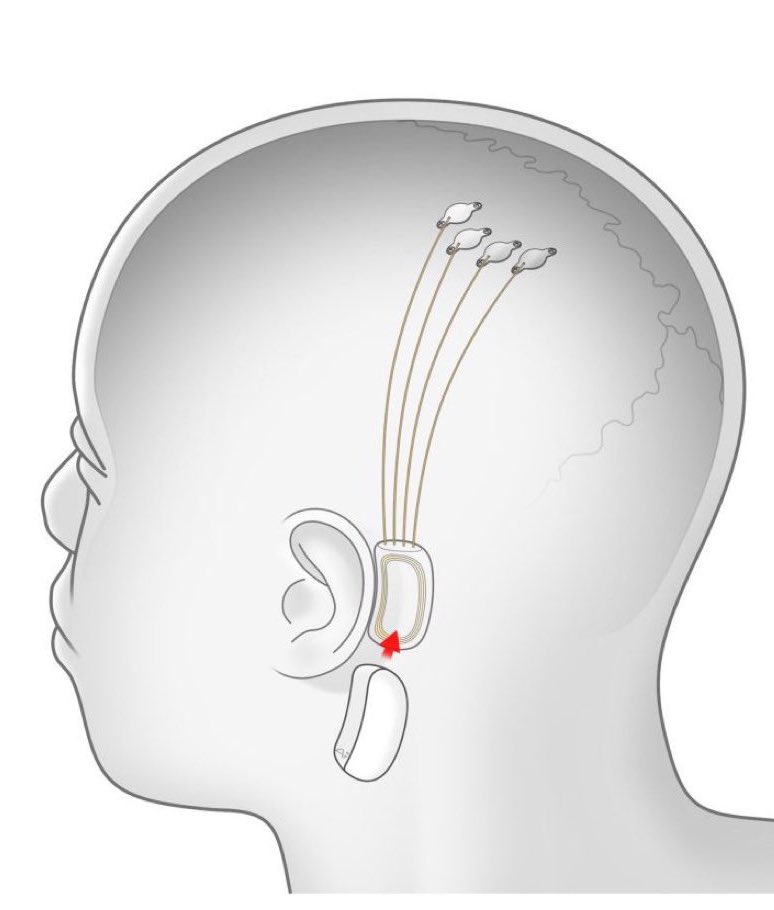

Elon Musk’s chip implant company Neuralink is looking for its first volunteer. They are looking for someone willing to have a piece of their skull removed so that a robotic surgeon can insert thin wires and electrodes into their brain.